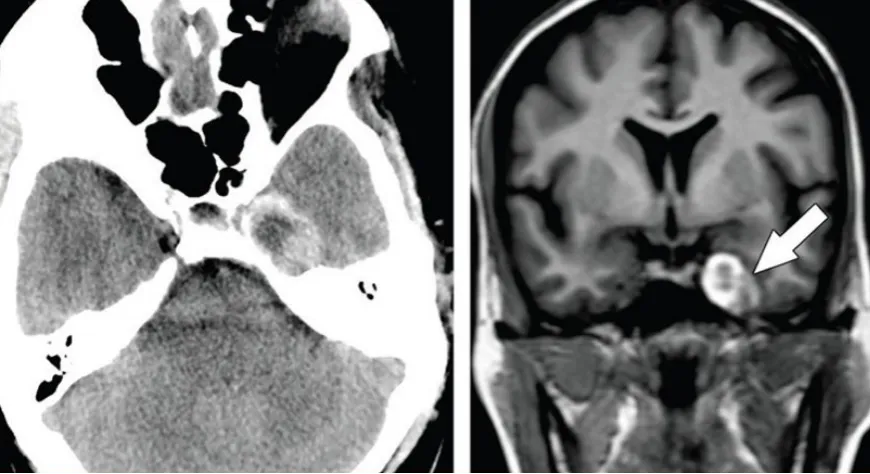

典型病例影像学表现

海绵窦区颈内动脉瘤

海绵窦区表皮样囊肿